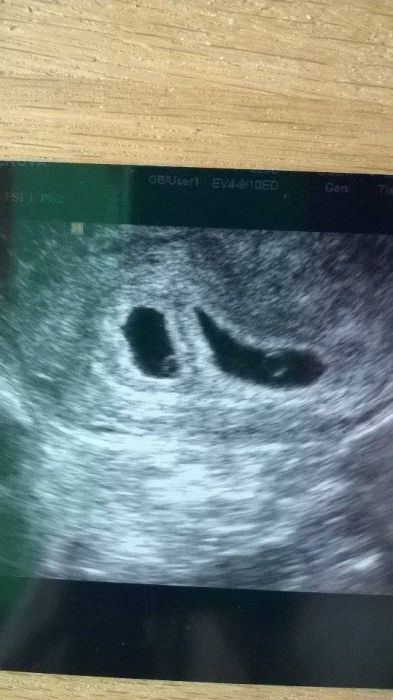

Ahoj zlatíčka, já jen hlásím, že dnes cca 5tt+4 a máme nakonec dvojčátka.... Zatím vše OK. Ale neraduji se předčasně. Další UTZ za týden ve ČT.

Lucisku, jeeee, pidata mrnavoucky :) moc gratuluju!!! Vzpominam si spravne, ze jsi v zacatcich diskuze psala, ze se dvojcatek obavas? :) Ja jsem se taky vzdy bala, ale pri tomto KETu jsem si uvedomila, ze bych za ne byla moc rada. Drzim palce, hlavne bud v klidu a uzivej si!!! Na utz jsi sve mimisky jeste nevidela, ne? To bych brala jako znameni, ze to nyni vsechno vyjde!! :*